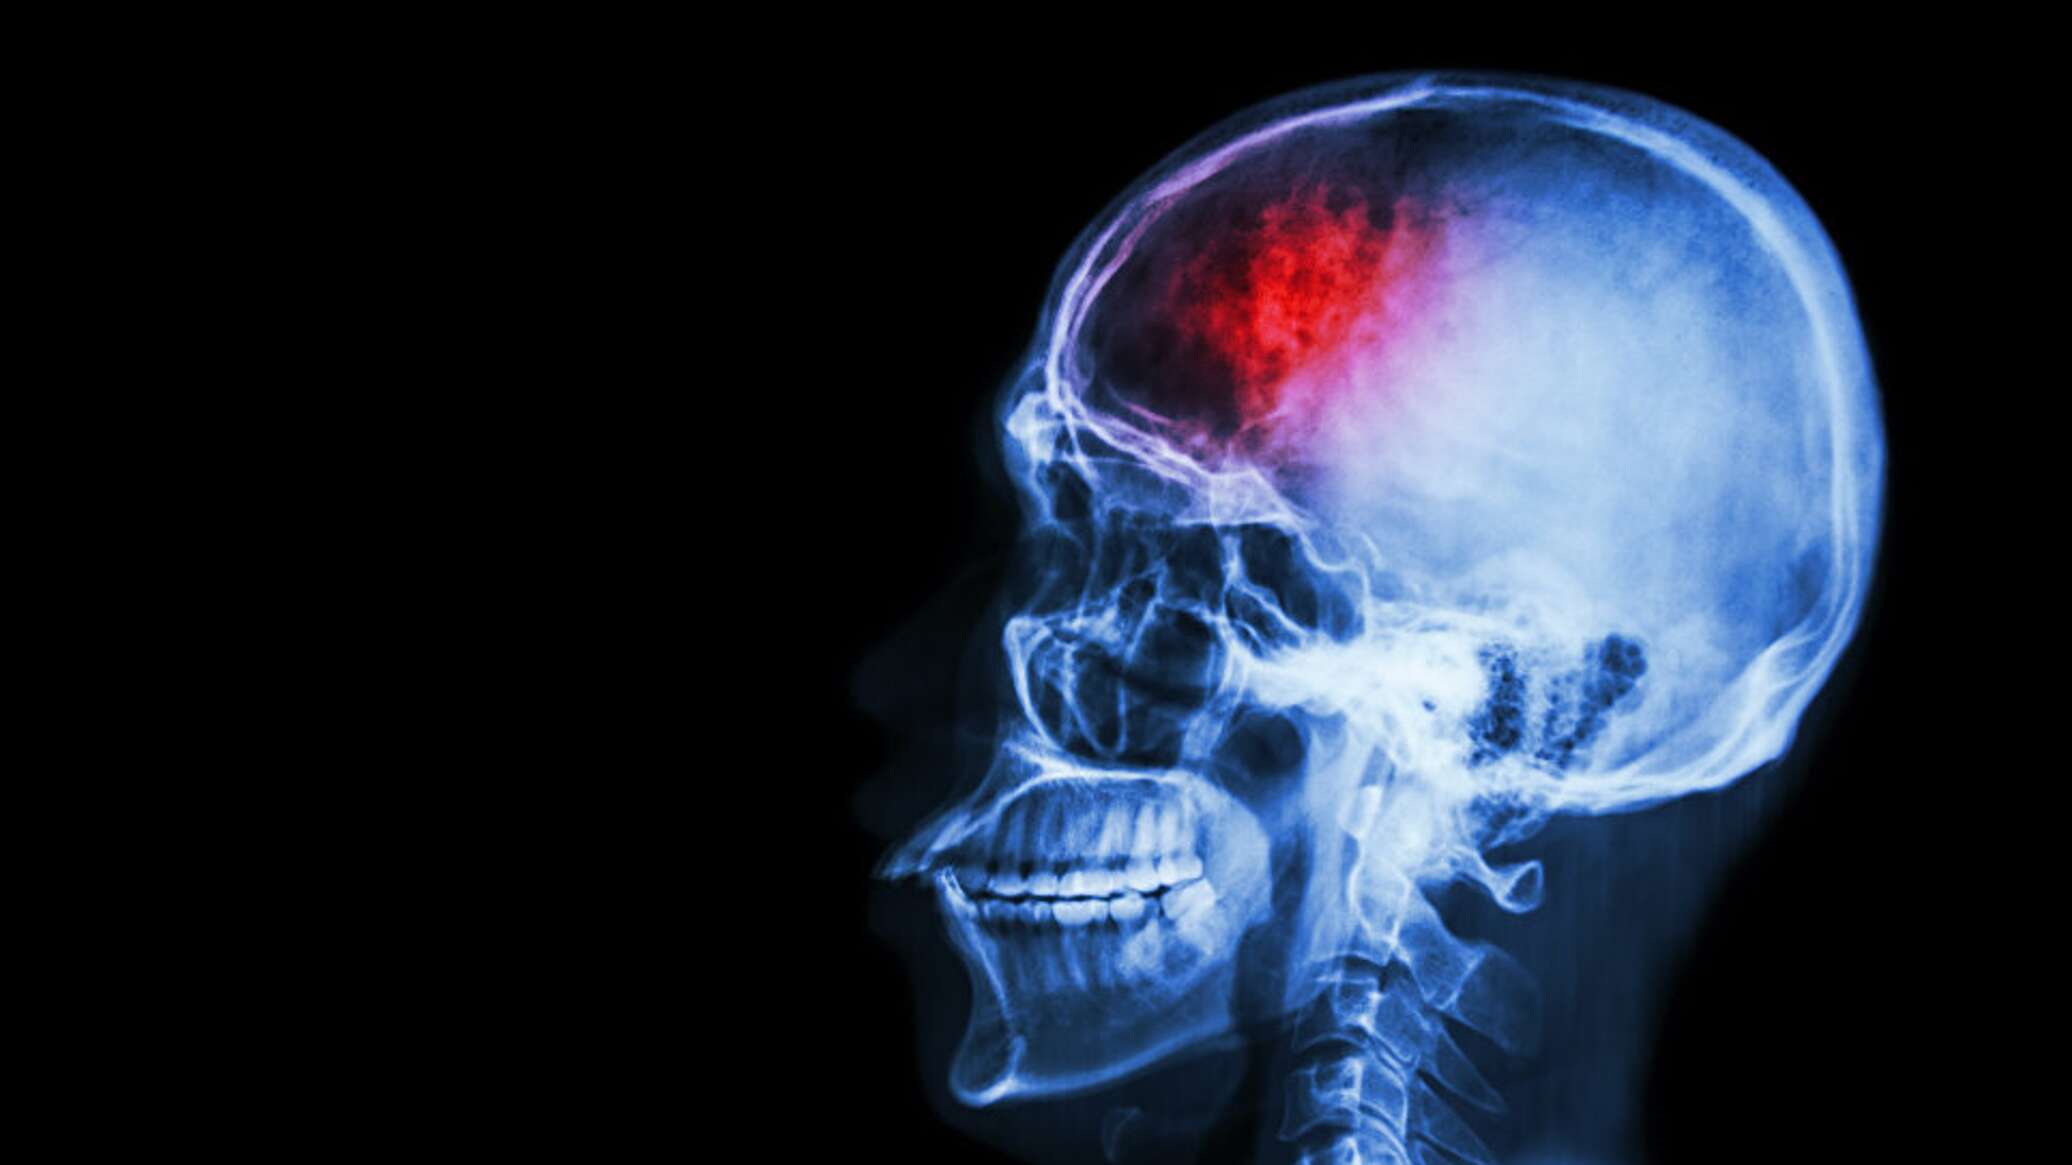

СИМФЕРОПОЛЬ, 29 окт – РИА Новости Крым. Всемирный день борьбы с инсультом отмечают 29 октября с 2004 года по инициативе Всемирной организации здравоохранения. О современном подходе в лечении и профилактике этого заболевания в эфире радио Спутник в Крыму рассказал заведующий неврологическим отделением для больных с острым нарушением мозгового кровообращения Республиканской клинической больницы Н.А. Семашко Яков Филатов.